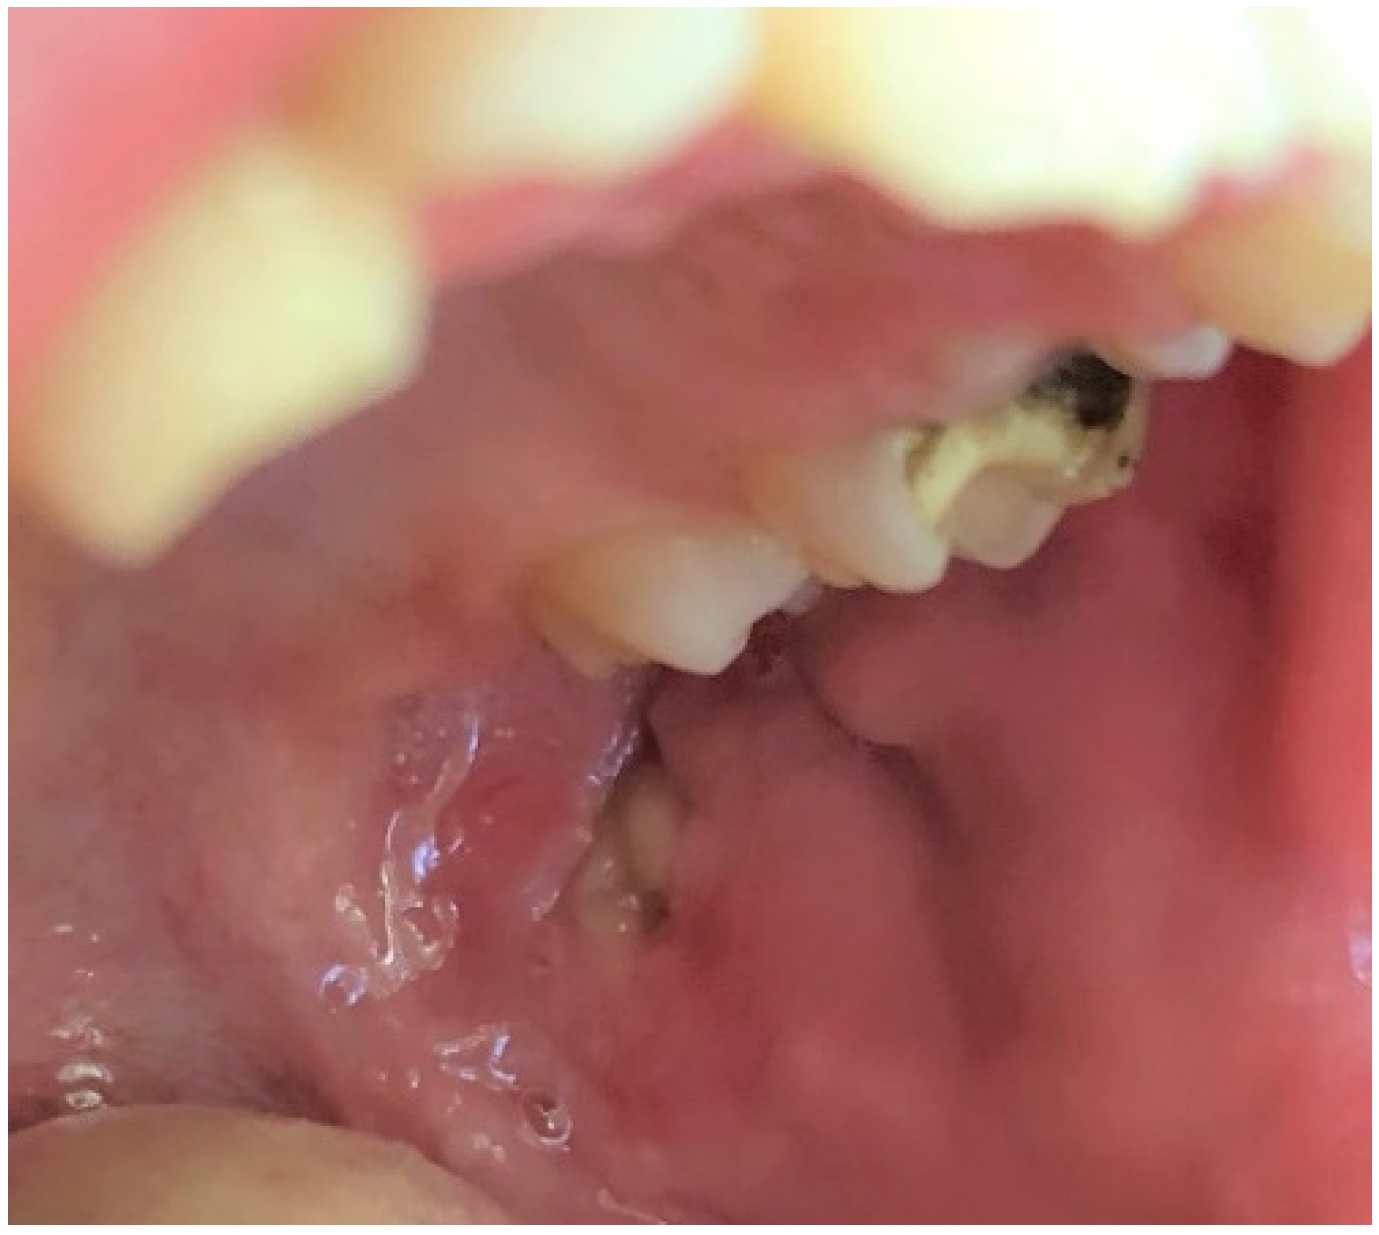

The incidence of pyogenic granuloma—4.2% (Figure 10)—was similar compared to the research carried out by Skinner et al. (4.1%) on 1525 patients aged 1–19 years [38]. This value was also close to the pooled global frequency (4.87%) presented in the most recent review, but lower than the European prevalence (8.82%) of this mucosal alteration revealed in the same article [1]. On the one hand, studies from the UK and Spain even showed a lower frequency than our figure or the European average, 3.06% and 2.2%, respectively [33,39]. On the other hand, Gultelkin et al., in her Turkey-based study, diagnosed pyogenic granuloma in 7% of all of her patients, and Sklavounou-Andrikopoulou et al. reported its incidence in a very high level of 35.1% in the Greek pediatric population [36,40]. In our study, children aged 7–13 and females were more frequently affected (the 5th most common diagnosis among girls, and 3rd among school-age children), which was also reflected in the previous findings [32,33,36,38].

Figure 10.

Pyogenic granuloma around 74 and 75 deciduous teeth in a school-aged female. In this case, pyogenic granuloma appears as a smooth, sessile mass with pink-reddish surface. Typically, the mass is painless and bleeds easily. Gingival irritation and inflammation due to poor oral hygiene—similar to this patient—may be a precipitating factor.